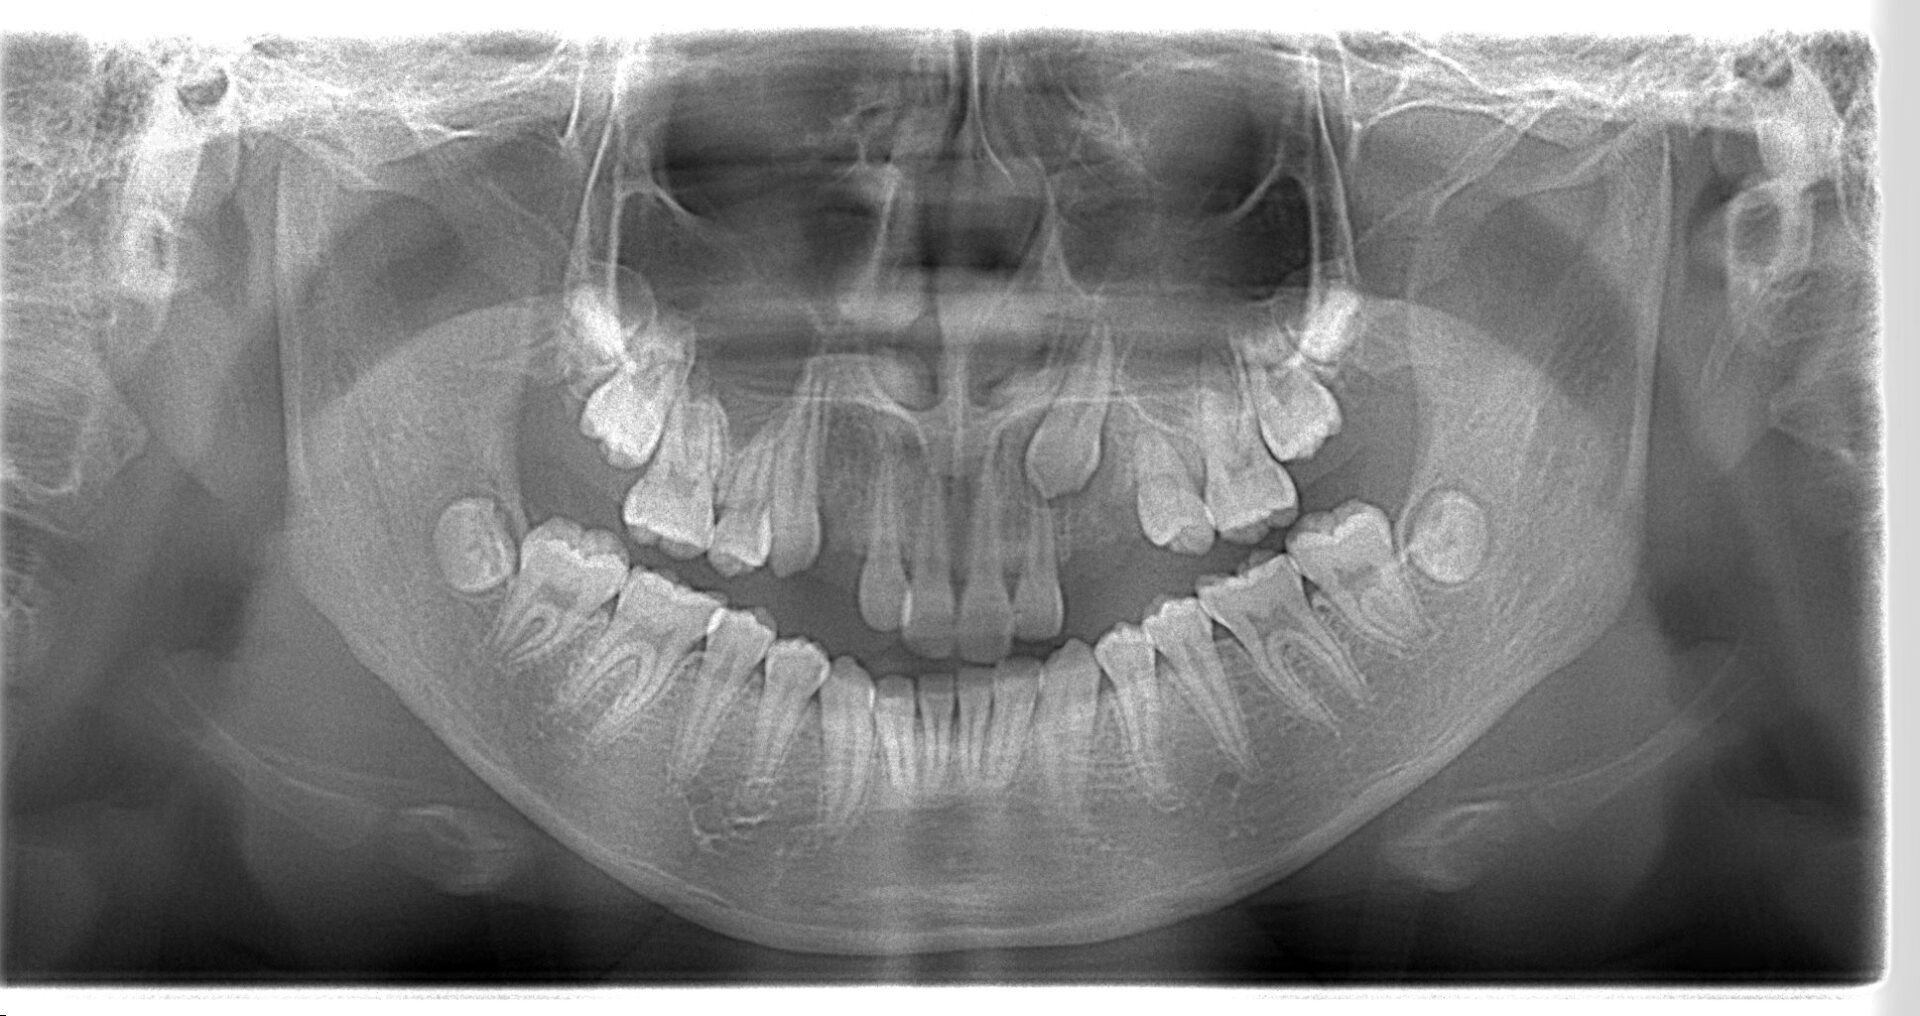

不正咬合が咀嚼機能に与える影響とは?噛み合わせの大切さ

「しっかり噛めていない気がする」 「食事に時間がかかる」「片側でばかり噛んでしまう」 このようなお悩みの背景に、不正咬合が関係して…[read more]